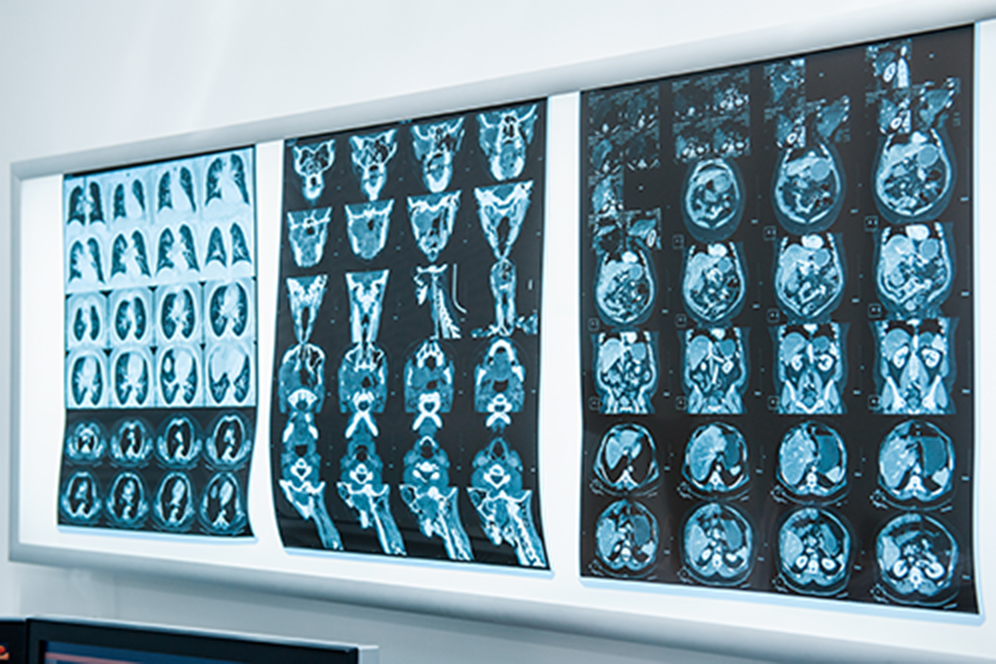

Darm- und Lungenkrebs sind die bekanntesten unter den häufigen Tumorerkrankungen. Was viele nicht wissen: Auch Kopf-Hals-Tumoren zählen – auf Platz sechs – zu den meistverbreiteten Krebsarten. In Deutschland erhalten allein etwa 13.000 Menschen pro Jahr die Diagnose Mundhöhlen- oder Rachentumor. Eine solche Erkrankung hat weitreichende Folgen: Patienten können teilweise nicht mehr richtig schlucken. Dadurch fallen Essen und Trinken schwer und auch das Sprechen ist – je nach Lage des Tumors – eingeschränkt. Mit der Sensibilisierungswoche für Kopf-Hals-Tumoren vom 21. bis 25. September 2020 will die Europäische Kopf-Hals-Gesellschaft (European Head and Neck Society, EHNS) auf die Tumorerkrankungen im Kopf-Hals-Bereich aufmerksam machen und über Ursachen und Behandlungsmöglichkeiten aufklären. Eine umfassende Versorgung erhalten Betroffene in spezialisierten Organkrebszentren, die von der Deutschen Krebsgesellschaft zertifiziert sind und somit hohe Standards erfüllen. Das Kopf-Hals-Tumorzentrum (Sprecher: Prof. Dr. Dr. h. c. Heinrich Iro und Prof. Dr. Dr. Marco Kesting) am Universitätsklinikum Erlangen war eines der ersten Zentren, die zertifiziert wurden und ist mittlerweile das größte Kopf-Hals-Tumorzentrum in Deutschland.

Zu den Kopf-Hals-Tumoren zählen neben Mundhöhlenkarzinomen, also z. B. Tumoren von Lippen, Zunge, Gaumen oder Speicheldrüsen, auch bösartige Tumoren des Rachens (Pharynxkarzinom), des Kehlkopfes (Larynxkarzinom), der Nase, der Nasennebenhöhlen sowie des äußeren Halses. Rauchen und regelmäßiger Genuss von Alkohol erhöhen das Risiko, an einem derartigen Tumor zu erkranken. Gerade bei jüngeren Menschen lösen Humane Papillomviren (HPV) die bösartigen Zellwucherungen aus. Diese Viren sind vor allem dafür bekannt, Gebärmutterhalskrebs zu verursachen; sie können aber eben auch im Kopf-Hals-Bereich Gewebeveränderungen hervorrufen. In den vergangenen Jahren ist die Wahrscheinlichkeit, an Kopf-Hals-Tumoren zu erkranken, insbesondere bei Frauen weltweit angestiegen. „Typische Beschwerden wie Heiserkeit, Schluckbeschwerden oder Halsschmerzen erscheinen vielen harmlos, sie können jedoch auf ernst zu nehmende Kopf-Hals-Tumoren hinweisen“, erklärt PD Dr. Antoniu-Oreste Gostian, Koordinator des Kopf-Hals-Tumorzentrums und Oberarzt der HNO-Klinik des Uni-Klinikums Erlangen. „Leider werden diese Krebsarten aufgrund der vermeintlich unbedenklichen Symptome oft erst im fortgeschrittenen Stadium diagnostiziert und behandelt. Vergehen die Beschwerden innerhalb von drei Wochen nicht von allein, sollte daher unbedingt ein HNO-Arzt konsultiert werden.“

Im Kopf-Hals-Tumorzentrum des Uni-Klinikums Erlangen stehen Patienten alle Behandlungsmöglichkeiten zur Verfügung: von minimalinvasiven Operationen mit Laser über robotergestützte Eingriffe und Radio-Chemotherapie bis hin zur Immuntherapie. Betroffene erhalten die individuell für sie passende Behandlung. Auch große Tumoren können operativ entfernt und fehlendes Gewebe durch Verpflanzung von Gewebe aus anderen Körperstellen, z. B. vom Unterarm oder Oberschenkel, entsprechend rekonstruiert werden. Kopf-Hals-Tumorpatienten profitieren am Uni-Klinikum Erlangen aber auch von Studien und Behandlungsmethoden, die andernorts noch nicht zur Verfügung stehen. „Mit unserem standardisierten Schmerzkonzept bieten wir hier jederzeit eine optimale Behandlung therapiebedingter Schmerzen. Dabei stimmen wir die Behandlung auf jeden Patienten individuell anhand seiner persönlichen Schmerzangaben ab“, ergänzt Dr. Gostian. „Darüber hinaus bieten wir eine Vielzahl von Hilfestellungen während und nach der Krebstherapie. So unterstützen unsere erfahrenen Logopäden Betroffene beispielsweise beim Sprechen und Schlucken. Ernährungstherapeuten geben zusätzlich Tipps für leicht zu schluckende und trotzdem nährstoffreiche und schmackhafte Gerichte. Für die Versorgung in der häuslichen Umgebung nach Abschluss der stationären Behandlung gibt der erfahrene Sozialdienst der HNO-Klinik jede mögliche Hilfestellung.“